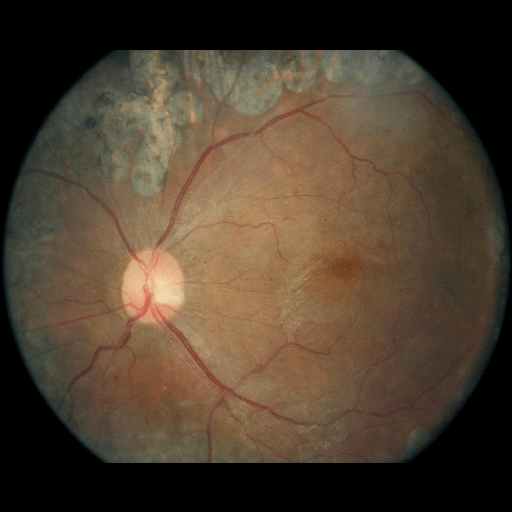

We conducted a case study on diagnosing diabetic retinopathy with ensembles of DL models. For benchmarking the performance of our ensemble-based solutions under the scheme described in Sec.3.3, we used two popular collections of diabetic retinopathy image data, the Kaggle Diabetic Retinopathy dataset [22] (hereafter referred to as “Kaggle-DR”) and the Messidor-2 dataset [23], each respectively consisting of and high resolution images. Diabetic retinopathy is graded into five SLs, as displayed in Figure 2. Following the problem setup used in previous papers [24], we trained models to distinguish the referable (SL2-4) cases from the non-referable ones (SL0 & SL1) (see Section B.1 for more detailed descriptions). We also tested our trained ensemble models on two o.o.d. image datasets (ImageNet [25] and CIFAR-10 [26]) to examine their capabilities of identifying o.o.d. inputs (see Section B in the supplementary materials).

The Kaggle-DR dataset comprises high resolution images. The presence of diabetic retinopathy is rated into five different SLs: no-DR (SL0), mild (SL1), moderate (SL2), severe (SL3), and proliferate (SL4), as illustrated in Figure 2. We divided the Kaggle-DR dataset into a development set and a test set, which respectively consisted of and images. The data in the development set were used to train and validate our Deep Learning (DL) models. The Messidor-2 dataset [38] that consisted of images was also used in our experiment as an additional dataset to test the true generalization performance of the models trained on the Kaggle-DR dataset. Images in Messidor-2 dataset were graded into the five SLs as in the Kaggle-DR dataset. Figure S.1 provides an illustration of the datasets used in our experiments.

The image data used in our experiment were all unified into square-shaped images with resolutions or in our preprocessing procedures. For training each neural network model, only images of the same resolution were used. The original images came with either of the two forms as exemplified in Figure S.2. In the first form (Figure 2(a)), the entire fundus was visible in the image. We cropped the image such that the fundus was tightly fitted inside the square. In the second form of input images shown in Figure 2(b), part of the fundus was not visible. We padded blank strips to make the image square-shaped and in a unified resolution. See the provided code for further details.